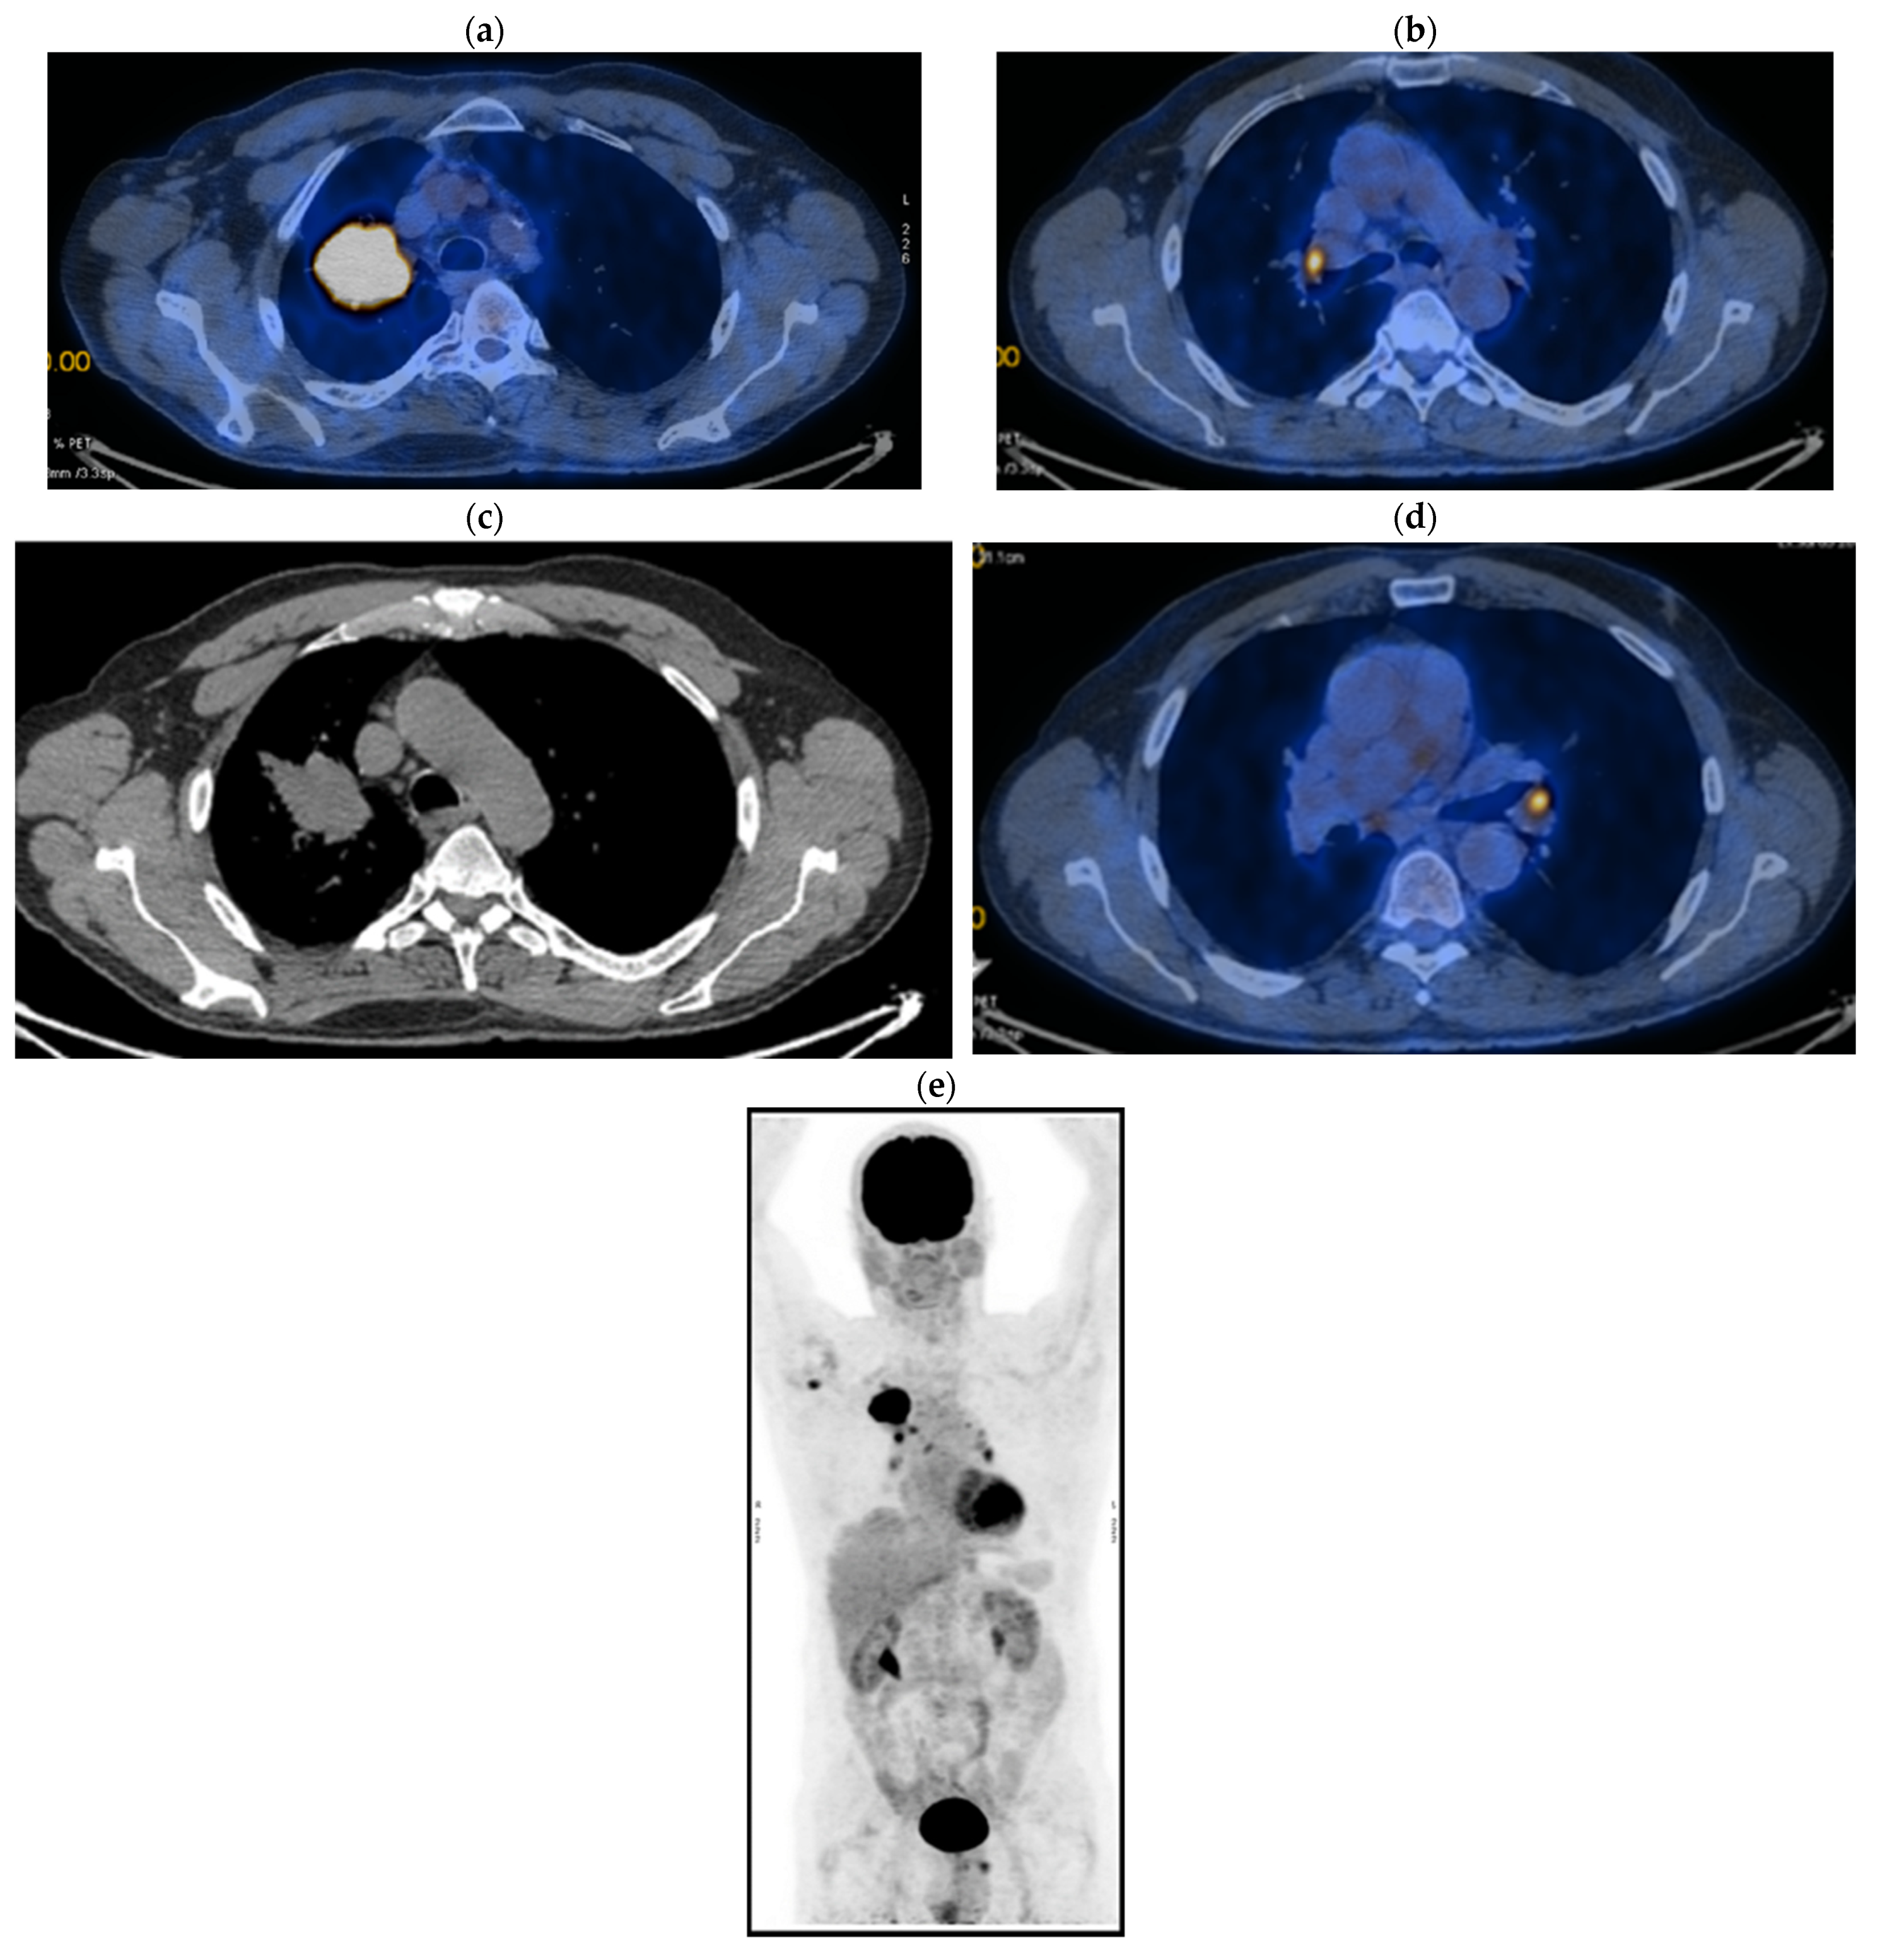

2. Case Presentation

2.1. Systemic Third-Line Therapy (4xDocetaxel) Was Initiated 04–07/2020

2.2. Monitoring 2022: Oncological Commission 1910/16.08.2022

2.3. Oncological Committee 07/25/2023 Recommended

- Consider rescue re-irradiation (SBRT), taking into account the current primary tumor dimensions of 24 × 34.2 mm on PET CT from 06/2023 and also the total dose previously administered (08–09/2020), the previously applied fractionation, the time between the two irradiations, the cellular repair time and the dose constraints for the organs at risk.